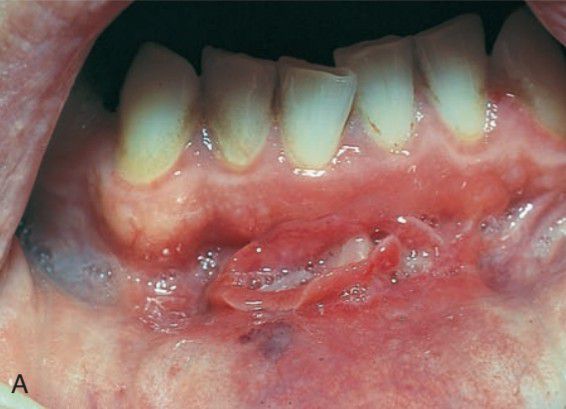

Crohns disease fissure

Oral manifestations include mucosal fissures and small, multiple, hyperplastic nodules on the buccal mucosa,producing a cobblestone appearance